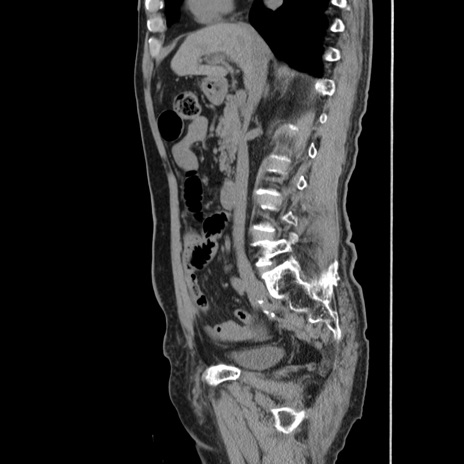

症例24(矢状断像)

【症例】80歳代男性

【主訴】左側腹部痛、嘔吐

【現病歴】本日早朝より左腹部に痛みあり。昼頃嘔吐認めたため、救急要請。

【既往歴】直腸癌(Mile手術)、胆摘

【身体所見】意識清明、BT 35.9℃、BP 221/93mmHg、SpO2 97%(RA) 、腹部:左ストーマ周囲に限局性の腹部膨隆あり。 膨隆部自発痛・圧痛あり・軟。

【データ】WBC 7700、CRP 0.09